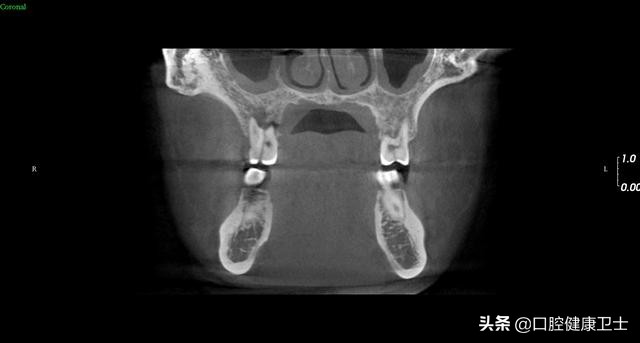

CT见,右上第一磨牙劈裂至髓室,左上第一磨牙同样,暂不处理。

CT见,右上第一磨牙劈裂至髓室底,没有保留可能性,建议拔除。左上第一磨牙,暂不处理。